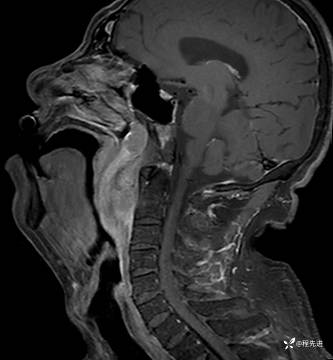

MRI平扫+增强:

T2压脂:

T1: